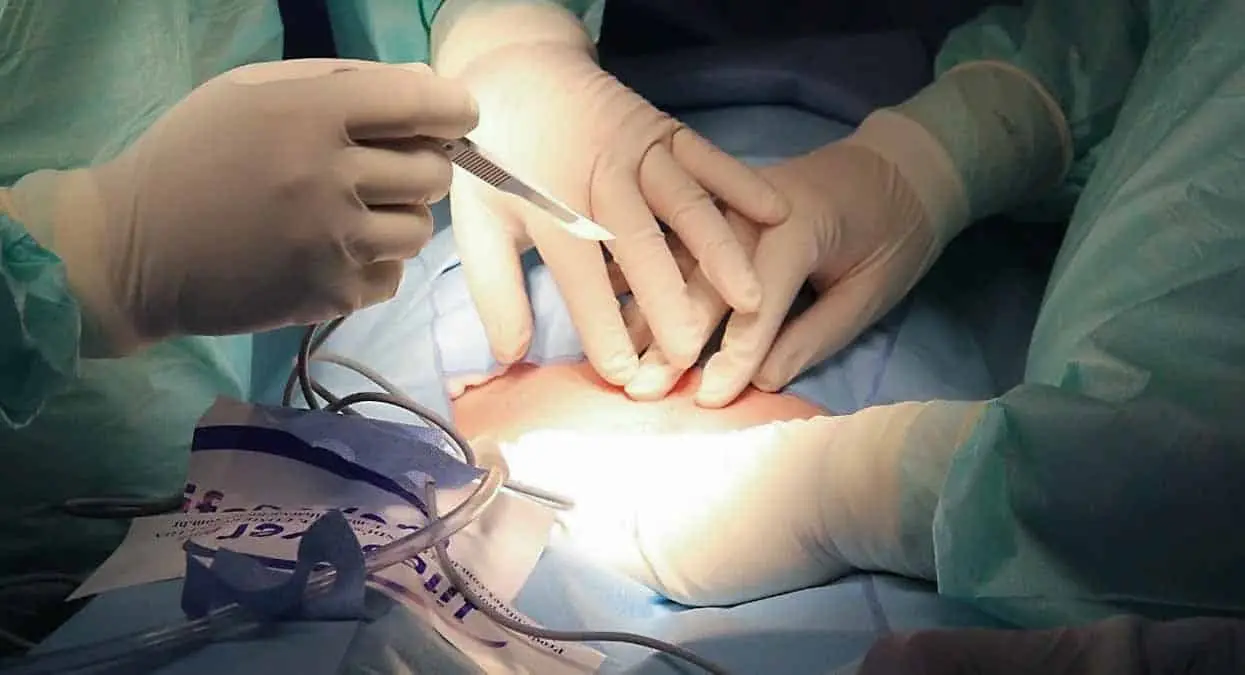

De acuerdo con la información, el joven acudió al Burdwan Medical College Hospital quejándose de fuertes dolores, por lo que cuando los doctores encontraron la causa de sus males, lo operaron con éxito, pues extirparon el objeto de aproximadamente 21 centímetros.

Debido a la introducción de un cuerpo extraño, el esófago del joven resultó severamente dañado, por lo que también fue arreglado, en una operación que duró poco más de dos horas.

Y no nada más el esófago resultó dañado, también sus intestinos, por lo que, en un futuro, requerirá de nueva cirugía para corregir el problema.

El médico tratante, Arindam Ghosh, explicó que, hace 20 días, la botella entró por el recto, provocando toda clase de dolores a su portador, lapso en que el afectado no pudo ir al baño y expuso su vida.